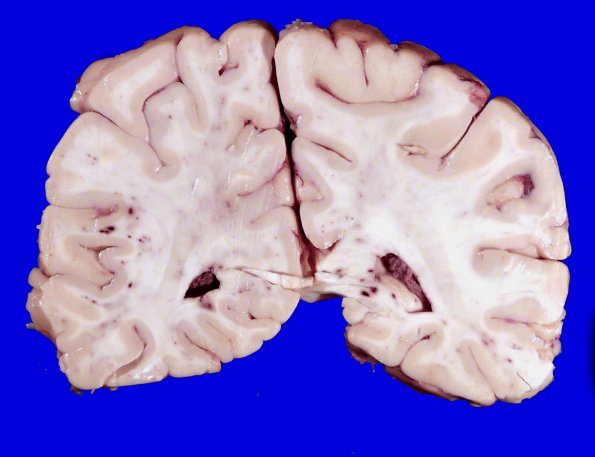

Several coronal sections were remarkable for numerous petechial hemorrhages mostly confined to the white matter suspicious for fat emboli.